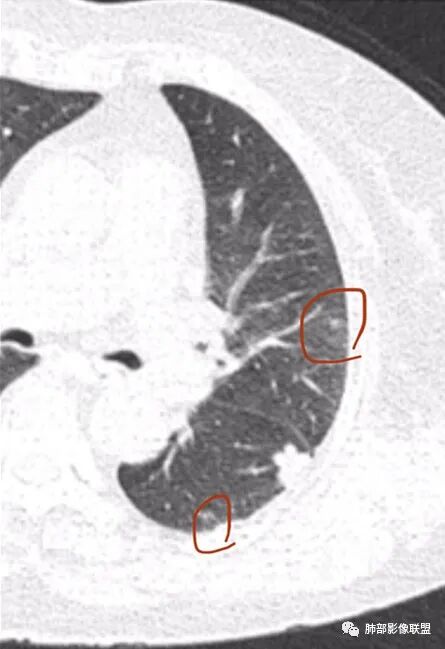

一、本例恶性征象较有特征的是脐凹征。

1.脐凹征:分叶状结节局部凹陷的部位受到血管阻力而形成,表现为血管进入分叶之间,脐凹相对比较对称光滑,近肺门侧多见,与血管走行方向一致。

2.95%见于恶性肿瘤,5%为炎性病变。

3.病灶显著强化不支持结核;边界清楚,肺门一侧波浪状改变,患者为老年女性,缺乏临床表现,尽管影像有一些炎性灶特点,但恶性肿瘤性病变不能除外。

二、早期结节型粘液腺癌诊断是腺癌诊断的难点之一,有哪些特点提示我们呢?根据曹悍波老师视频的总结如下:

1.中老年女性多见,单发,发病部位常位于双肺下叶胸膜下或叶间胸膜下,考虑与粘液重力分布有关。

2.50%左右为圆形,表现为椭圆形的结节生长方向与支气管垂直,其他的为不规则形,大部分病灶具有一定的恶性征象,少数不典型。

3.表现为混合磨玻璃结节,边界似清非清,为粘液向外飘散;实性结节收缩力弱,是由于粘液张力抵消了一部分纤维的收缩力,由于生长的不对称常导致收缩力不对称。

4.粘液腺癌的破坏力相对较低,血管及支气管破坏轻,可见血管造影征及空气支气管征;侵袭力弱,发展慢。

5.部分病灶需要与炎性病变、良性结节相鉴别,因此,临床抗炎治疗和短期随诊复查是非常必要的。